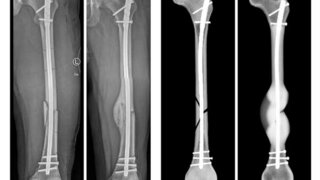

Studie am Universitätsklinikum UlmComputersimulation prognostiziert Heilungsverlauf von Frakturen In fünf bis zehn Prozent der Fälle kommt es zu Komplikationen bei einer Frakturheilung. Am Universitätsklinikum Ulm (UKU) wurde nun eine Computersimulation entwickelt, die den Heilungsverlauf vorhersagen soll. 26.09.2022 Gesellschaft